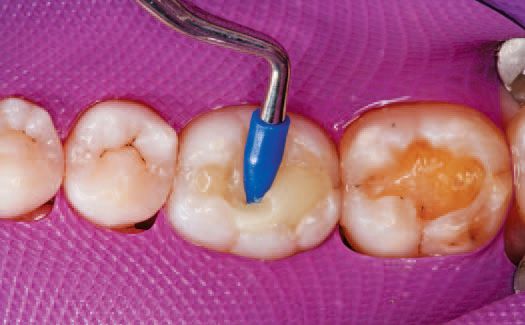

A single increment of Tetric EvoCeram Bulk Fill in shade IVA was then placed in the preparation of tooth No. 30 (Fig. 9), and shaped first with an OptraSculpt® sphere attachment (Fig. 10), then with an OptraSculpt pyramid attachment (Fig. 11). The final anatomy was contoured using a P1 plugger (Fig. 12). As a final step before finishing, the restoration was light cured with the LED curing light (Fig. 13).